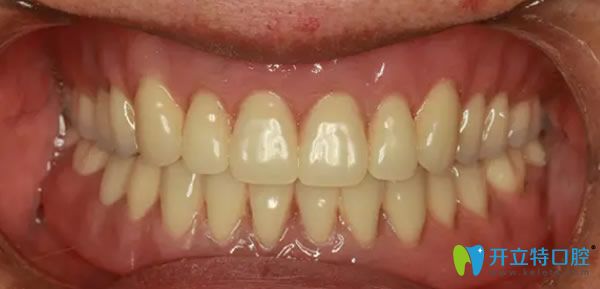

經(jīng)過6個月的恢復(fù)時間,來院復(fù)查,醫(yī)生說,牙槽骨和種植體緊密結(jié)合,可以為外婆裝上牙冠了,看來種植牙的成功率挺高的。術(shù)后外婆全口種植牙后的效果媲美真牙,整個人看起來也精神了好多,吃什么也更有胃口了,外婆激動的說,擁有這一口美麗的大白牙,瞬間覺得我返老還童啦!哈哈!

全口牙缺失種植后的效果好不好?效果圖見證實(shí)力: